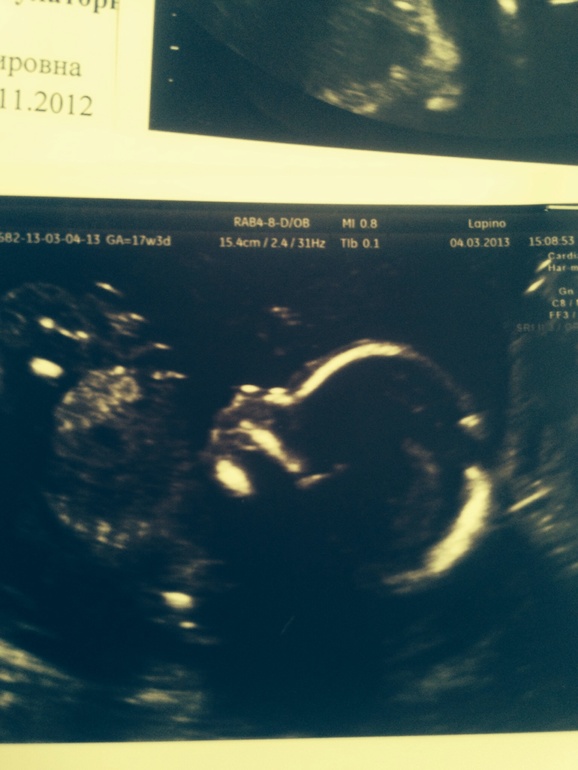

Сын

на втором снимке нос острее, подбородок также более острый, губы разные и даже форма головы - ну это на мой взгляд.